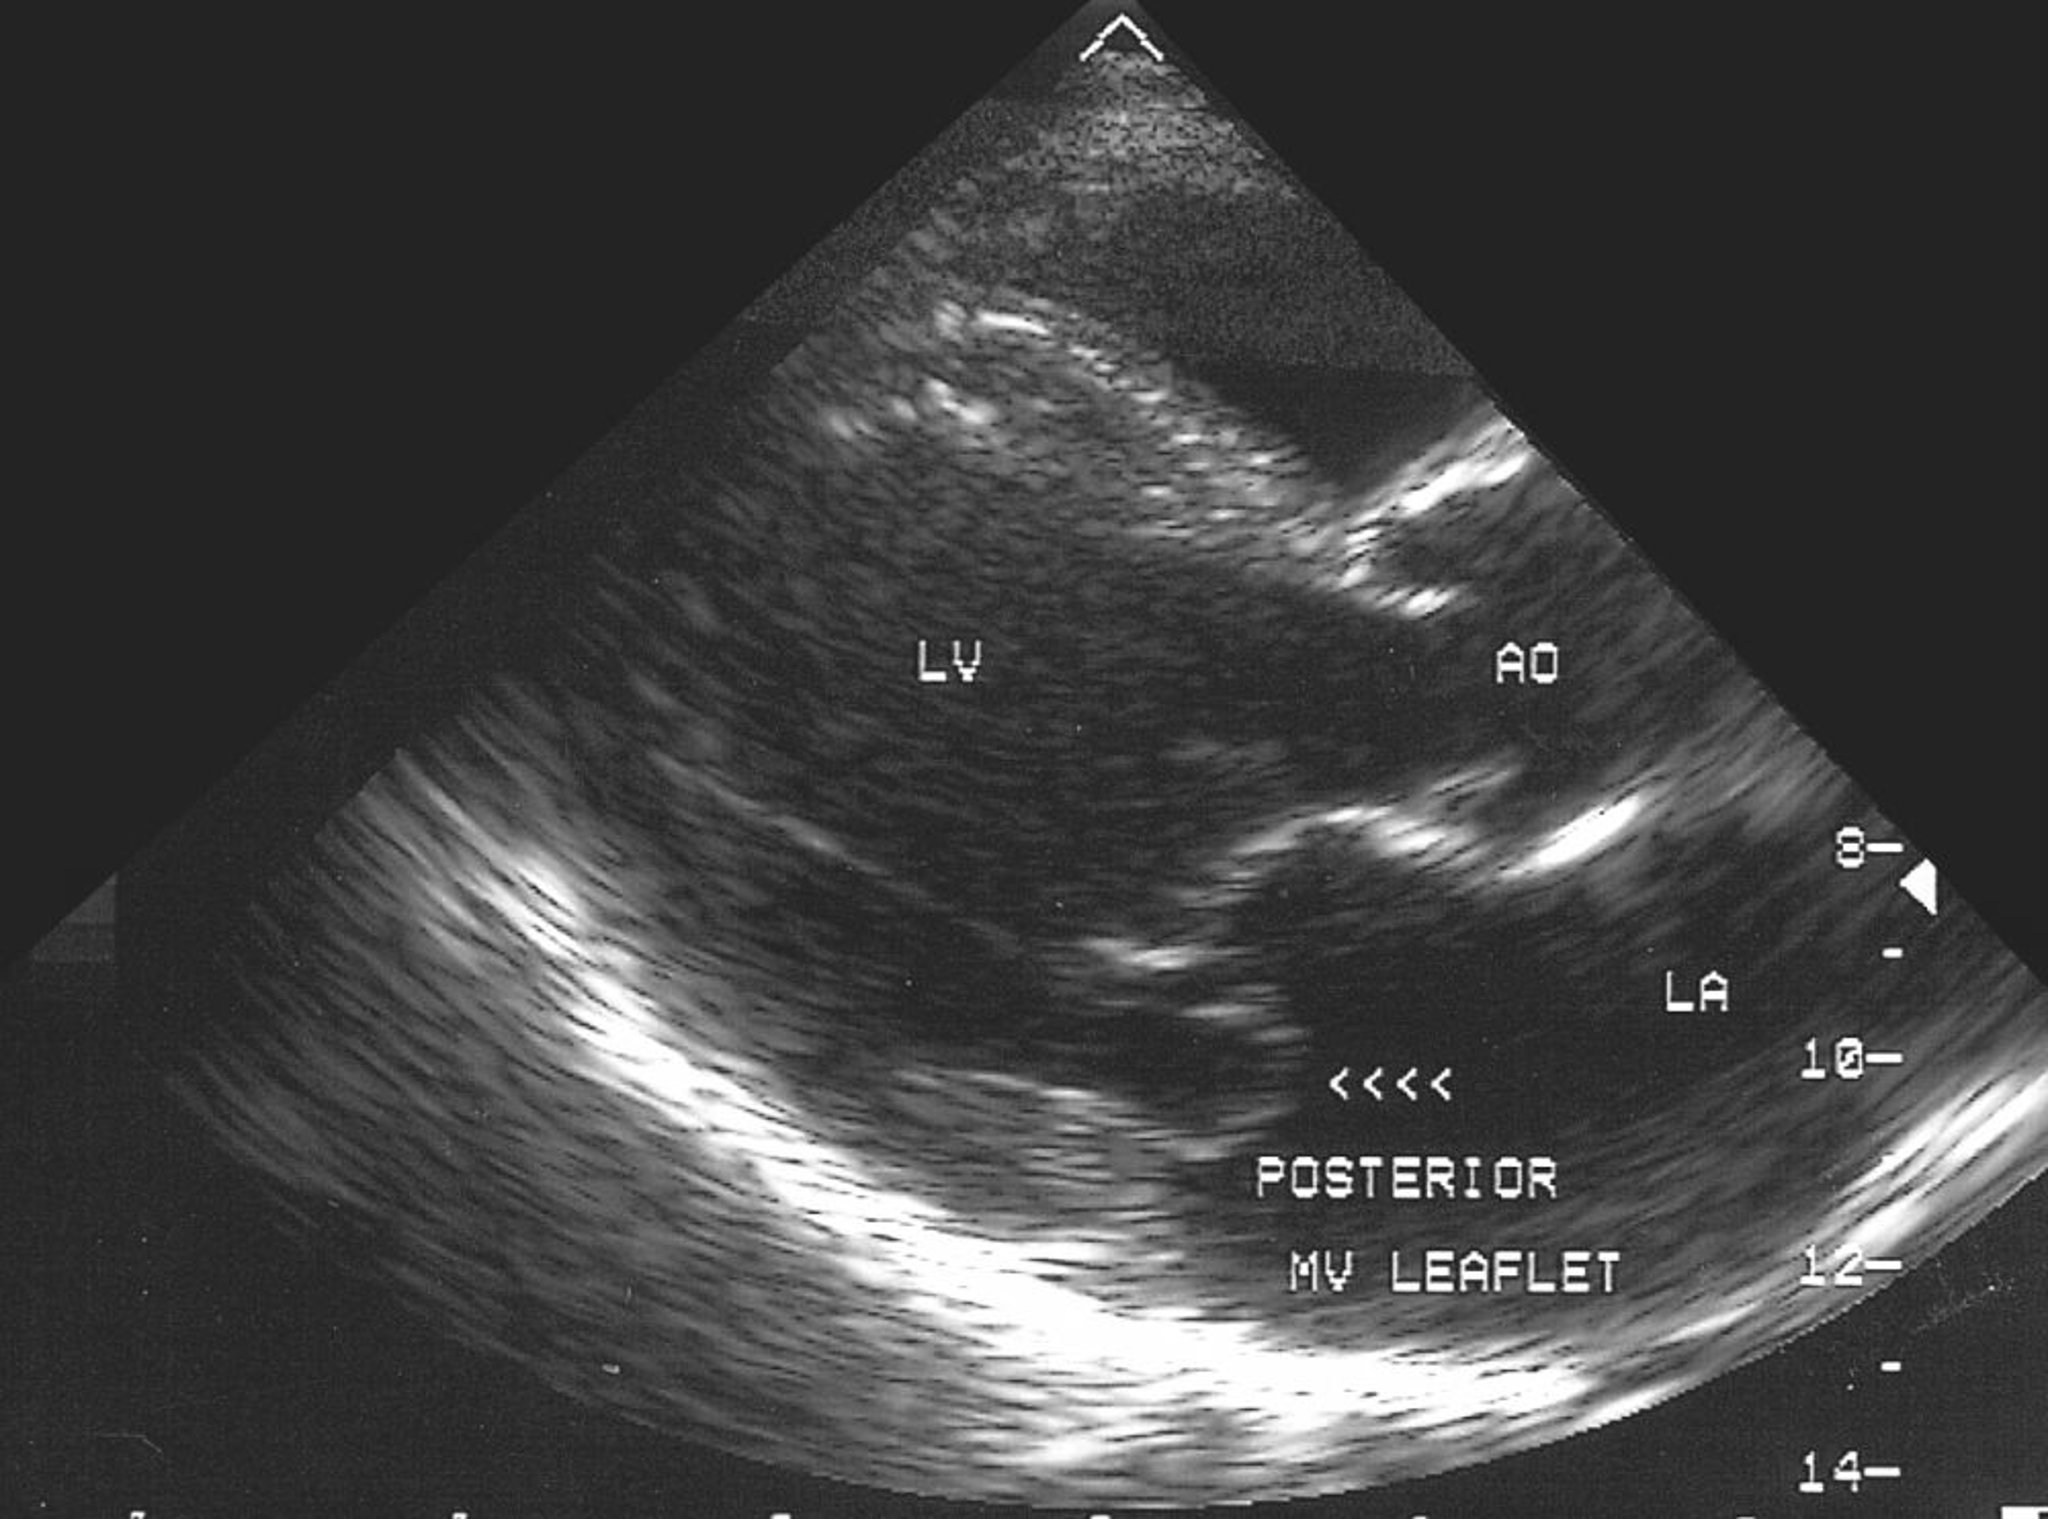

Пролапс митрального клапана (Эхокардиограмма)

Это эхокардиографическое изображение показывает пролапс задней створки митрального клапана в левое предсердие (LA).